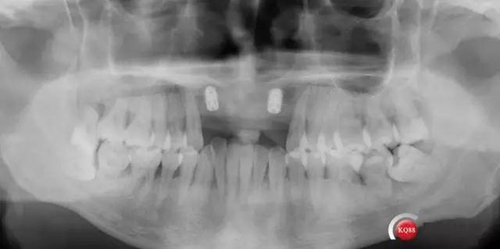

術(shù)后CBCT

靜靜等待3個月全景,未見異常